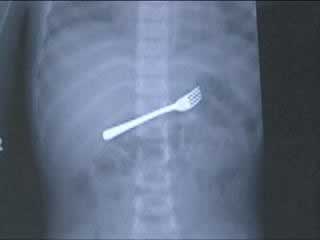

一把叉子